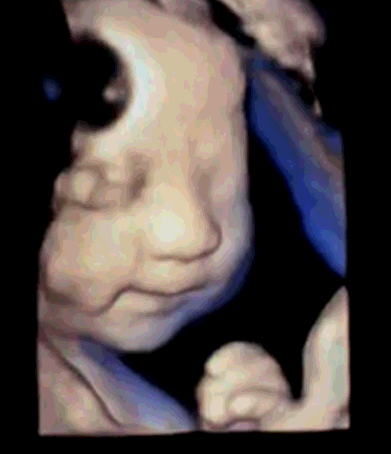

四维彩超的全称为四维彩色超声诊断仪,是目前世界上最先进的彩色超声设备。四维彩超的诊断资料有利于医生检测出各种异常,对于胎儿的成长发育做出准确的判断。那么四维彩超上的数据具体应该怎么看,美琳达妇儿医院四维彩超医生毕春英和您说一说关于四维彩超的那些事儿!

感受、聆听已经无法满足我们对胎宝宝的爱,只有“清晰地看见”才能让我们欣喜若狂……